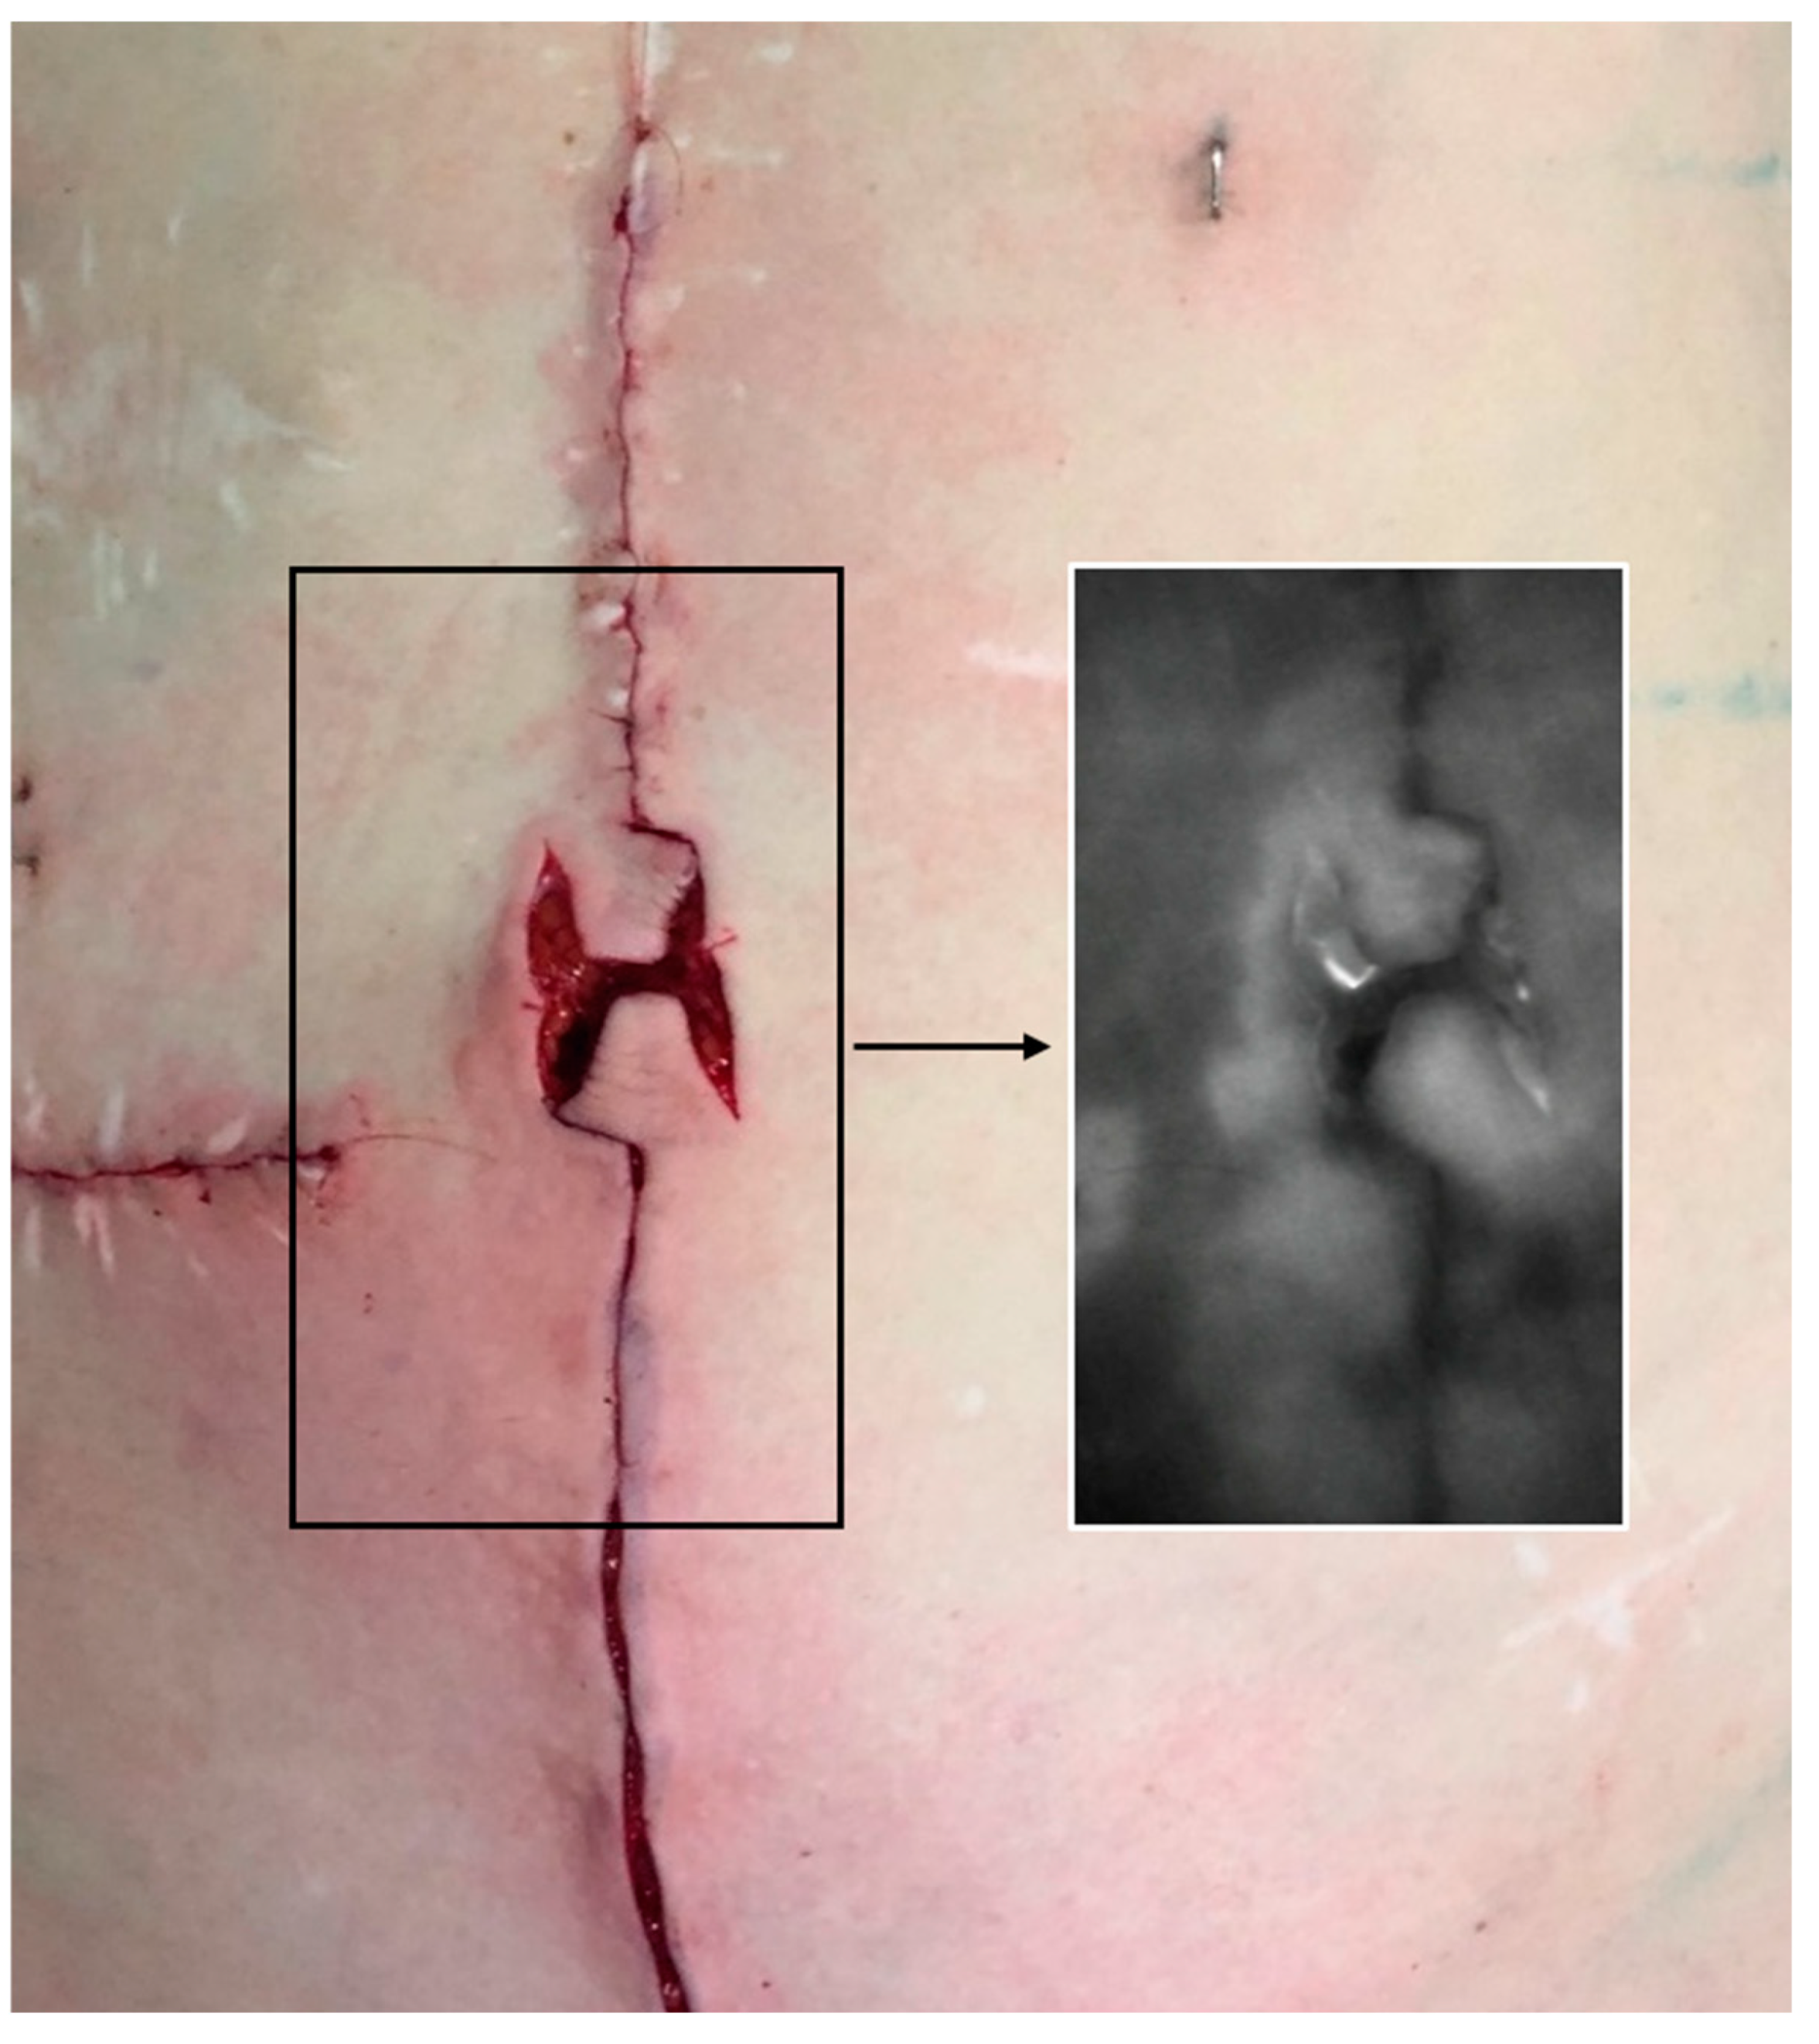

4. Indocyanine Green Fluoroscopy

As is standard in our department when performing abdominal wall reconstruction with tissue resection, we routinely performed indocyanine green (ICG) fluoroscopy. Analysis was conducted after closure of the midline and localized subcutaneous defatting. Topographic perfusion analysis was performed after intravenous injection of 25 mg indocyanine green (ICG-Pulsion® 5 mg/mL, PULSION Medical Systems SE, Feldkirchen, Germany), using the handheld IC-FlowTM device (Diagnostic Green LLC, Farmington Hills, MI, USA) (Figure 5).

Figure 5. Indocyanine green fluoroscopy. We routinely performed indocyanine green (ICG) fluoroscopy. Analysis was conducted after closure of the midline and localized subcutaneous defatting. ICG fluoroscopy demonstrates sufficient perfusion of the flaps.